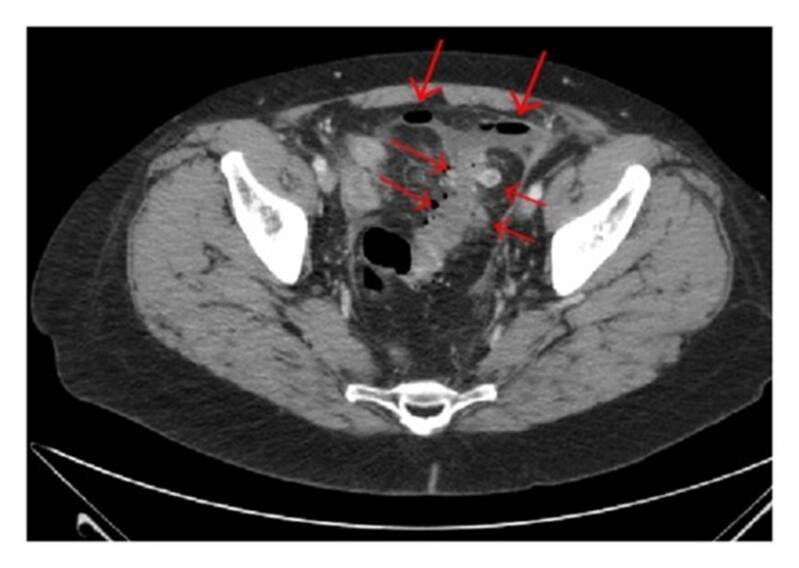

foto hierboven: duidelijk verschil tussen diverticulose en diverticulitis

Neemt het abces te grote proporties aan, dan volstaat een antibioticakuur niet meer. Bij vermoeden van een ernstige diverticulitis wordt je doorverwezen naar het ziekenhuis voor een CT-scan van de buik of een radiografie met contrastmiddel. Daarnaast kan ook een echografie helpen om een duidelijk beeld te schetsen van de uitstulpingen. (Door die scan met contrastvloeistof weet ik dat mijn (bijna dagelijkse) lichte buikpijn te wijten is aan diverticulose of meerdere divertikels).